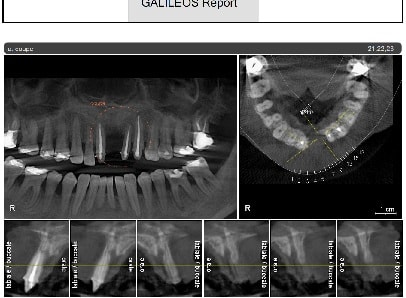

Je suis omnipraticien, je fais pas mal de 8 et 3 incluses, de kystes, de ROG, sinus et pose une petite centaine d’implants par an. Je me suis « offert » une Pano 3D en juillet après longue et mûre réflexion. En voici la teneur globale :

Je me suis évité de très mauvaises surprises en chir : en vrac, kyste apical 22,23,24 avec perfo nasale, perfo linguale sur un comblement alvéolaire de 36, des fractures radiculaires sagittales en pagaille, canal supplémentaire sur 33 ou34, fenestration de tables externes, etc…

SIRONA Orthophos avec Galliléos pour l'implanto, 2 licences (poste pano et secrétariat grand écran), le micro qui va avec et tout, 85 K€